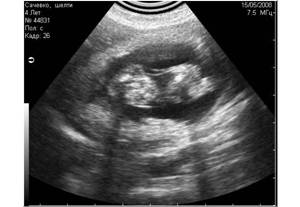

Рис. 9. Истинные эхоакустические тени, возникающие позади конкрементов в мочевом пузыре. |

Рис. 10. А вот и сами камни. |